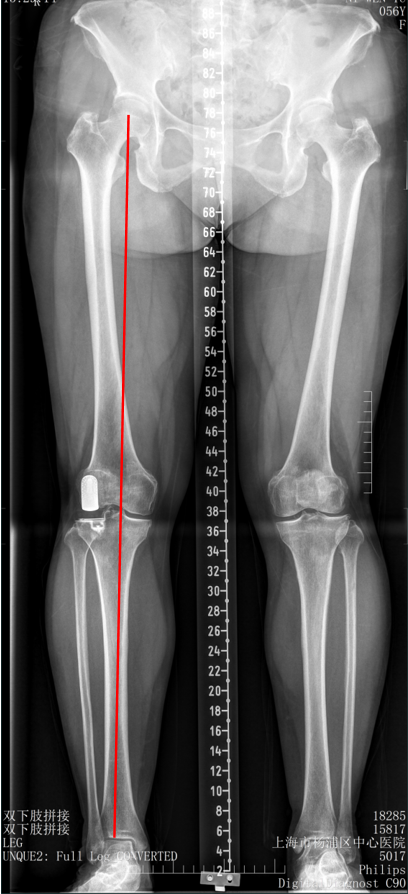

五、一期双单髁置换LINK:registered: SLED假体位置

双间室OA行Bi-UKA

正位片标准胫骨和股骨假体位置

AP位假体位置:内侧和外侧单髁分别按照各自的手术原则独立开展,假体的位置也按照各自的标准进行考量,需要综合考量的是胫股角,关节线,中央髁间隆突。

侧位片标准胫骨和股骨假体位置

侧位假体位置:内侧和外侧单髁分别按照各自的手术原则独立开展,假体的位置也按照各自的标准进行考量。

双间室OA行Bi-UKA术后内侧假体周围骨折ORIF